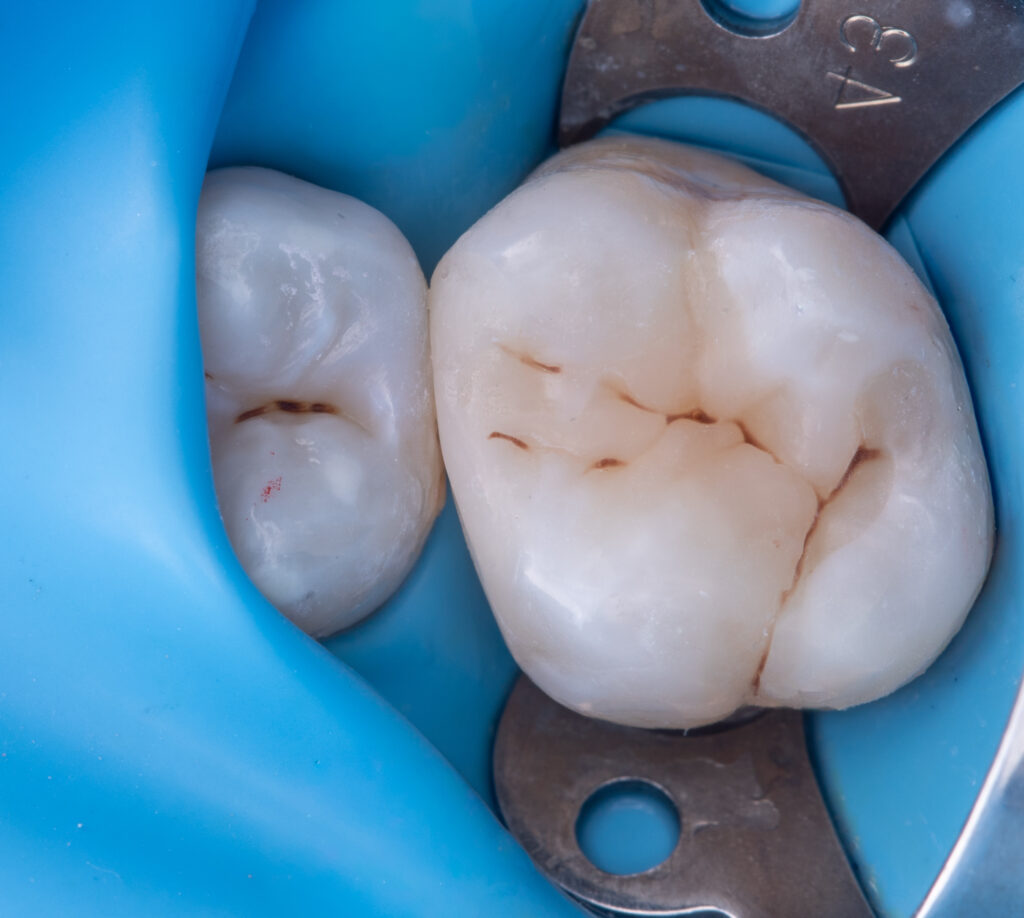

Treatment of caries on tooth 1.6 with preservation of proximal contact on the crista transversa and restoration of the secondary tooth anatomy.

A sectional matrix system by Garrison and a wedge by Palodent were used.

The composite materials applied were: Asteria A2B for wall reconstruction, EvoCeram Dentin 2 as an opaque dentin composite, NeoSpectrum A2 for anatomical modeling, and Enamel brown stain for characterization.